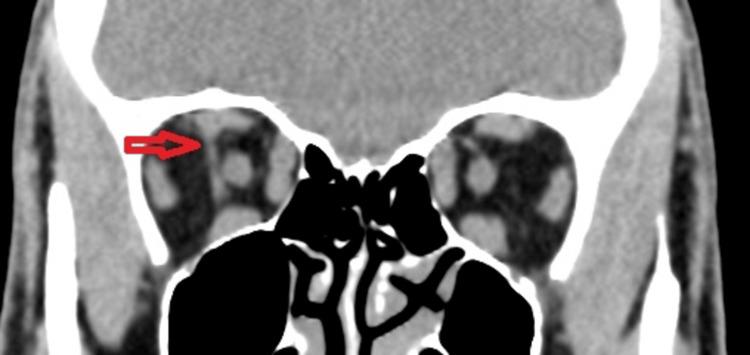

In this case report, we present the rare occurrence of supernumerary extraocular muscles (SEOM) in a 35-year-old male with hyperthyroidism. SEOMs are unusual anatomical variations involving extraocular muscles that deviate from the typical muscle arrangement in the eye. While SEOMs are rare, they can have diverse clinical manifestations, including restrictive strabismus and lid abnormalities. In this case, the patient displayed right-sided lid retraction and an asymmetrical palpebral aperture, which raised concerns about a potential association with thyroid eye disease. However, imaging revealed that the SEOM was anatomically connected to the superior rectus muscle, possibly contributing to the observed lid retraction. Understanding the complexities of SEOM and its potential interactions with conditions like thyroid ophthalmopathy is crucial for accurate diagnosis and management. Further research is needed to fully comprehend the development and clinical impact of SEOMs due to their rarity and limited knowledge in the medical literature.

在本病例报告中,我们呈现了一名35岁甲状腺功能亢进男性罕见的额外眼外肌(SEOM)情况。SEOM是涉及眼外肌的异常解剖变异,偏离了眼睛中典型的肌肉排列。虽然SEOM很罕见,但它们可具有多种临床表现,包括限制性斜视和眼睑异常。在本病例中,患者表现为右侧眼睑退缩和睑裂不对称,这引发了对其与甲状腺眼病潜在关联的担忧。然而,影像学显示SEOM在解剖学上与上直肌相连,这可能是观察到的眼睑退缩的原因。了解SEOM的复杂性及其与甲状腺眼病等病症的潜在相互作用对于准确诊断和管理至关重要。由于SEOM在医学文献中罕见且知识有限,需要进一步研究以全面理解其发育和临床影响。